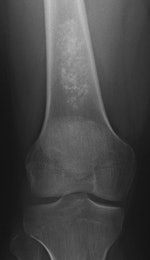

Incidental findings -- also known colloquially as "incidentalomas" or findings that are discovered unintentionally -- are on the rise around the world. Only about 1% of these findings are harmful to the patient, but still, in 1% of patients they're a problem, so what's a radiologist to do about them?

Incidentalomas are a relatively new phenomenon that account for approximately 15% to 20% of all findings. This is primarily because, for instance, the number of CT scans has shot up from around 3 million in 1980 to around 80 million in 2012 over the past decade in the U.S., he added. Due to the population increasing and getting older, the frequency of incidentalomas is only going to rise, he added. Beyond that, there's also a sophistication issue; the technology around the world has become more sensitive, so radiologists see things today they didn't 15 years ago.